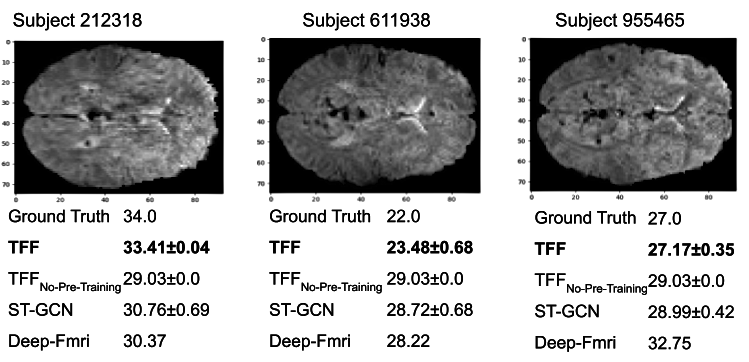

Fig. 4 depicts three representative samples from the age prediction task. The figure presents the age predictions of all models for three subjects from the HCP test set, along with the ground truth and a representative slice from each of the scans.

Table 3 depicts the performance of all models evaluated on the age prediction task from the HCP dataset. This task is formulated as a regression task, where the models are expected to predict the exact age of each subject. Each of the models in this evaluation applies a standard regression head and optimizes an L1 loss w.r.t the ground truth age labels. As can be seen in the table, TFF shows a clear advantage over the other techniques. Compared to ST-GCN, the second best model in this evaluation, TFF yields an absolute improvement of 0.4, 2.6 on L1 and L2 respectively, and a relative improvement of 23% in NMSE. Interestingly, the gap in performance is even larger with respect to the TFF baseline, for which TFF improves in absolute scores of 0.4, 3.2 for L1 and L2, and a relative improvement of 26% in NMSE. This can be attributed to the importance of the pre-training procedure, which allows TFF to learn an effective representation for 4D fMRI data prior to the fine-tuning procedure. \textcolorblackStatistical significance for the age prediction task can be found in Appendix G.